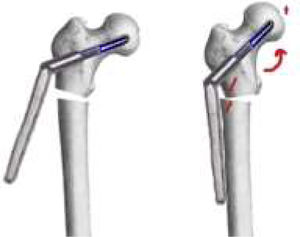

The goal of the surgical technique is to overcorrect the varus deformity to get a final 150° valgus angle at the femoral neck. It is also important that the distal part of the proximal side of the nonunion be in contact with the distal part (diaphyseal bone), to get a dynamic compression from the first postoperative day (Fig. 1).

It is recommended to use a 150° plate for “low” nonunions, and a 135° plate for “high” nonunions (more proximal nonunions). If we use the 150° plate, the cephalic screw should follow the central axis of the femoral neck. Nevertheless, If we use the 135° plate, to get 150° of valgus at the neck, the path for the cephalic screw must be 15° of varus (Fig. 2). The tip of the screw should be as near to the center of the hip as possible. Anyway, a slight downward position of the tip of the screw is possible (as seen in Fig. 1), if necessary, to avoid the same hole as the previous implant.

Over-valguization of the nonunionIn this moment, the DHS (of at least 6 holes) is introduced to the previously introduced cephalic screw. To correct the position of the femoral head, the plate should be placed just over the diaphyseal bone. To accomplish this, a Lowman retractor is recommended. Softly, the retractor is tightened, and the plate comes to the diaphyseal bone, reducing the nonunion (Fig. 6).